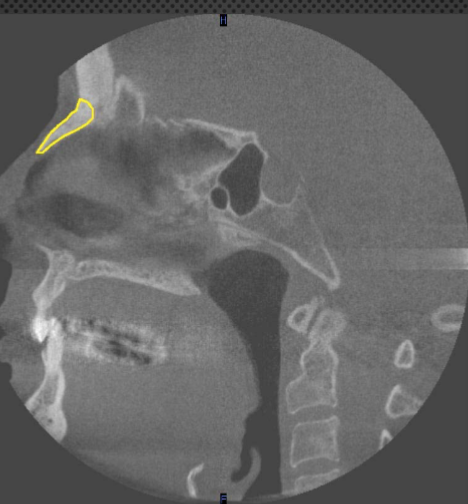

sagittal

what plane is this

coronoid process

identify the structure